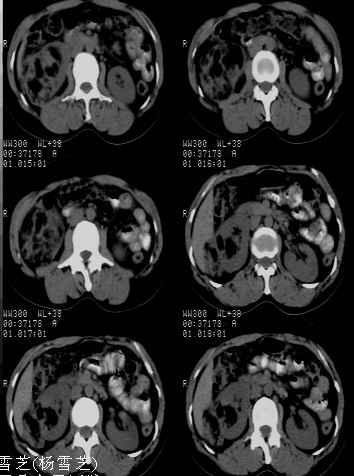

结果收到---右肾细胞癌;单就影像表现是应该首先考虑血管平滑肌脂肪瘤。

病理是有可能搞错不过可能性不大,不过这个确实不能报右肾细胞癌,真难

该病理结果应该送高级别医院做病理会诊,否则会影响影像医师今后的判断。免疫组化结果也并未公布,结果非常可疑。应进一步证实。